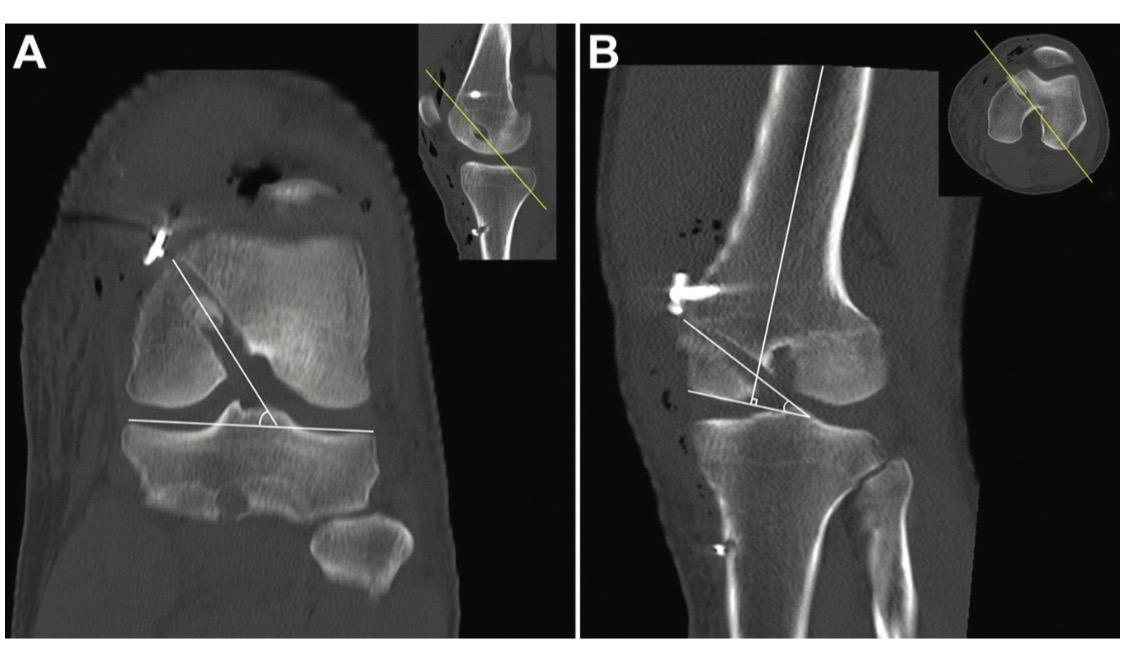

后交叉韧带重建。后交叉韧带(PCL)重建手术中,适当的隧道位置、隧道角度和移植物角度对于维持PCL移植物的稳定性和机械性能至关重要!